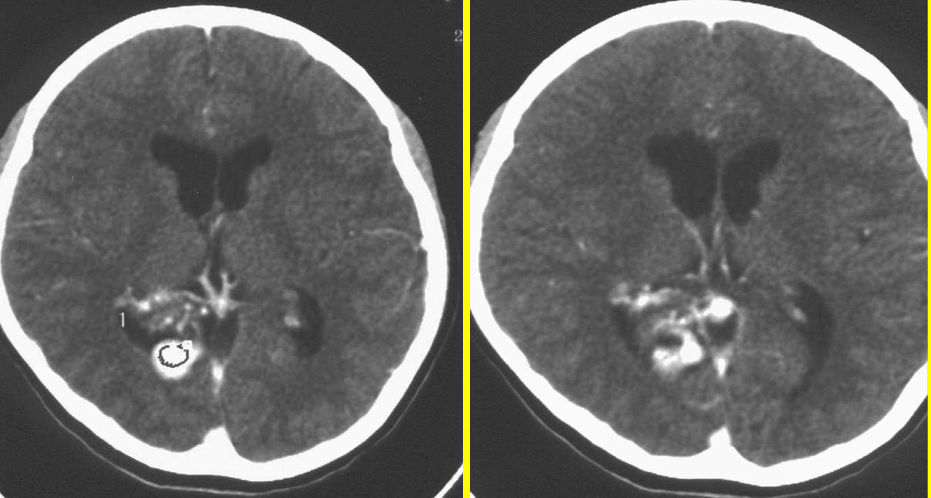

一例脑血管畸形患者

图片尺寸3648x2736

脑梗还是脑穿通畸形

图片尺寸394x395脑动静脉畸形影像学特征 脑动静脉畸形影像学特征